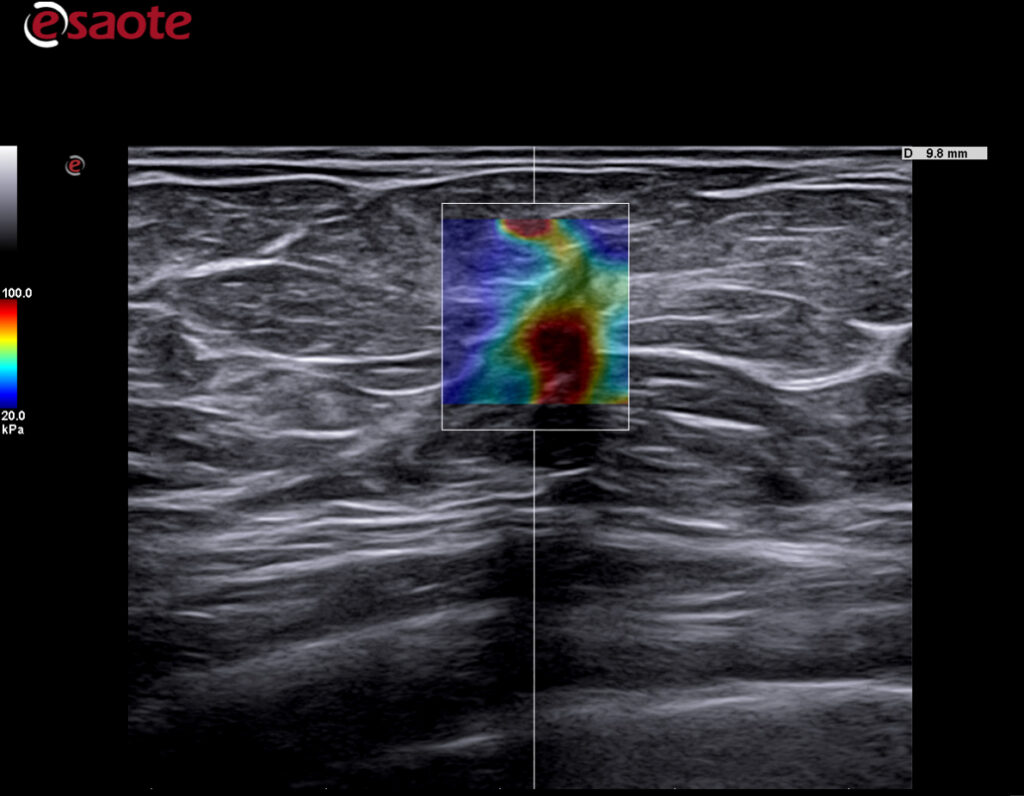

Kliniske bilder.

ElaXto

ElaXto (strain) lisens gir deg mulighet til å evaluere stivheten i et valgt område i real-time. Esaote har vært en pioner og stått fremst innenfor dette feltet i mange år. Dette benyttes innenfor mange områder som MSK, Bryster og Tyridea, Lever, Urologi(prostata) og gynekologi. -

ElaXto advanced

Advanced ElaXto et tilvalg til ElaXto lisensen -